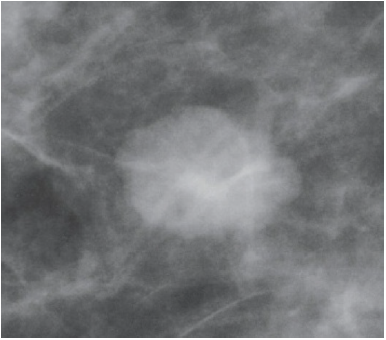

Paciente de 64 anos, sem história familiar de câncer de mama, sem queixas mamárias, comparece ao consultório com resultado de mamografia de rastreamento. Antecedentes: mamoplastia redutora há 20 anos. O laudo não apresenta classificação segundo BI-RADS, mas descreve nódulo oval, hiperdenso, margens microlobuladas, medindo 1,0x0,8cm em quadrante superolateral da mama esquerda. Ao exame físico: mamas médias sem alterações palpáveis. Abaixo imagem do exame. Assinale a alternativa que apresenta qual a melhor conduta para seguimento do caso.

Figura 1. Lesão em mamografia de rastreamento.